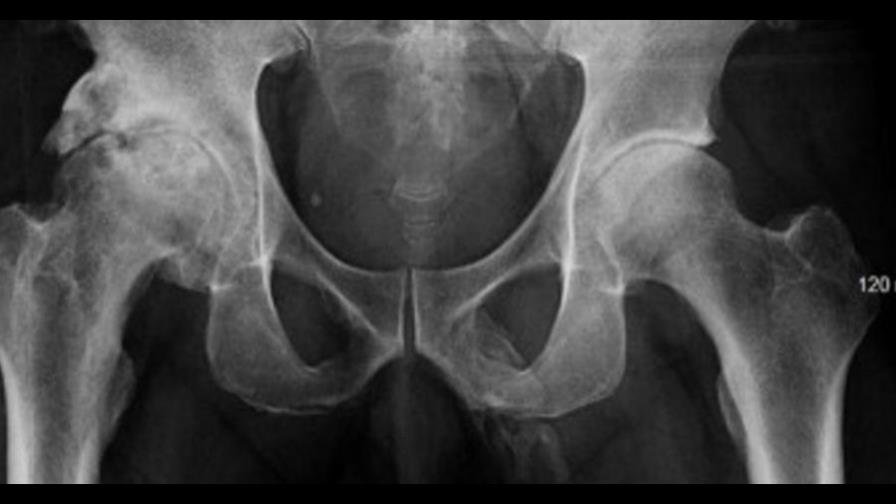

Tal cual como lo lees, el pene de este hombre está convirtiéndose en hueso. Los médicos lo diagnosticaron cuando le tomaron una radiografía en la pelvis para comprobar alguna lesión o fractura. En lugar de esto, hallaron una calcificación en el pene del hombre.

Además de un leve dolor, que el hombre atribuyó a su edad, no presentó ningún otro tipo de síntomas sobre esta condición. El hombre había acumulado sales de calcio en su tejido blando, que luego se endureció en una extensa placa a lo largo de todo su pene.